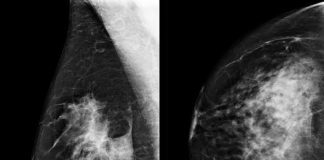

Um quadraro amarelo indica onde um sistema de inteligência artificial (IA) encontrou câncer escondido dentro do tecido mamário.

Um novo estudo revela que o Google AI é frequentemente melhor na detecção de câncer de mama do que médicos reais.